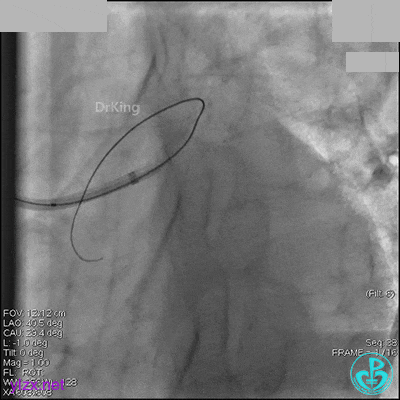

AL 1.0指引导管到位,简单短时尝试导丝不能顺利通过前降支或回旋支病变。改变策略处理右冠脉病变,计划植入2枚支架。AL指引导管到位,Sion blue导丝到达右冠脉远端。导丝通过后1.5mm及2.5mm球囊14~16atm充分扩张中段病变。

右冠脉中段充分扩张后欲植入3.5×38mm支架时,支架难以通过中远段扭曲处,且指引导管、导丝弹出飞扬。反复尝试导丝重新到达右冠脉远端时通过不顺利,局部造影剂滞留,远端血流接近3级。